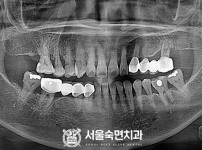

상악동거상술, 뼈이식 / 숙면임플란트 11개 - 포인트임플란트 (이*정님)

해당 게시물은 의료법 제56조에 의거하여 로그인 후 열람이 가능합니다.

구분 임플란트